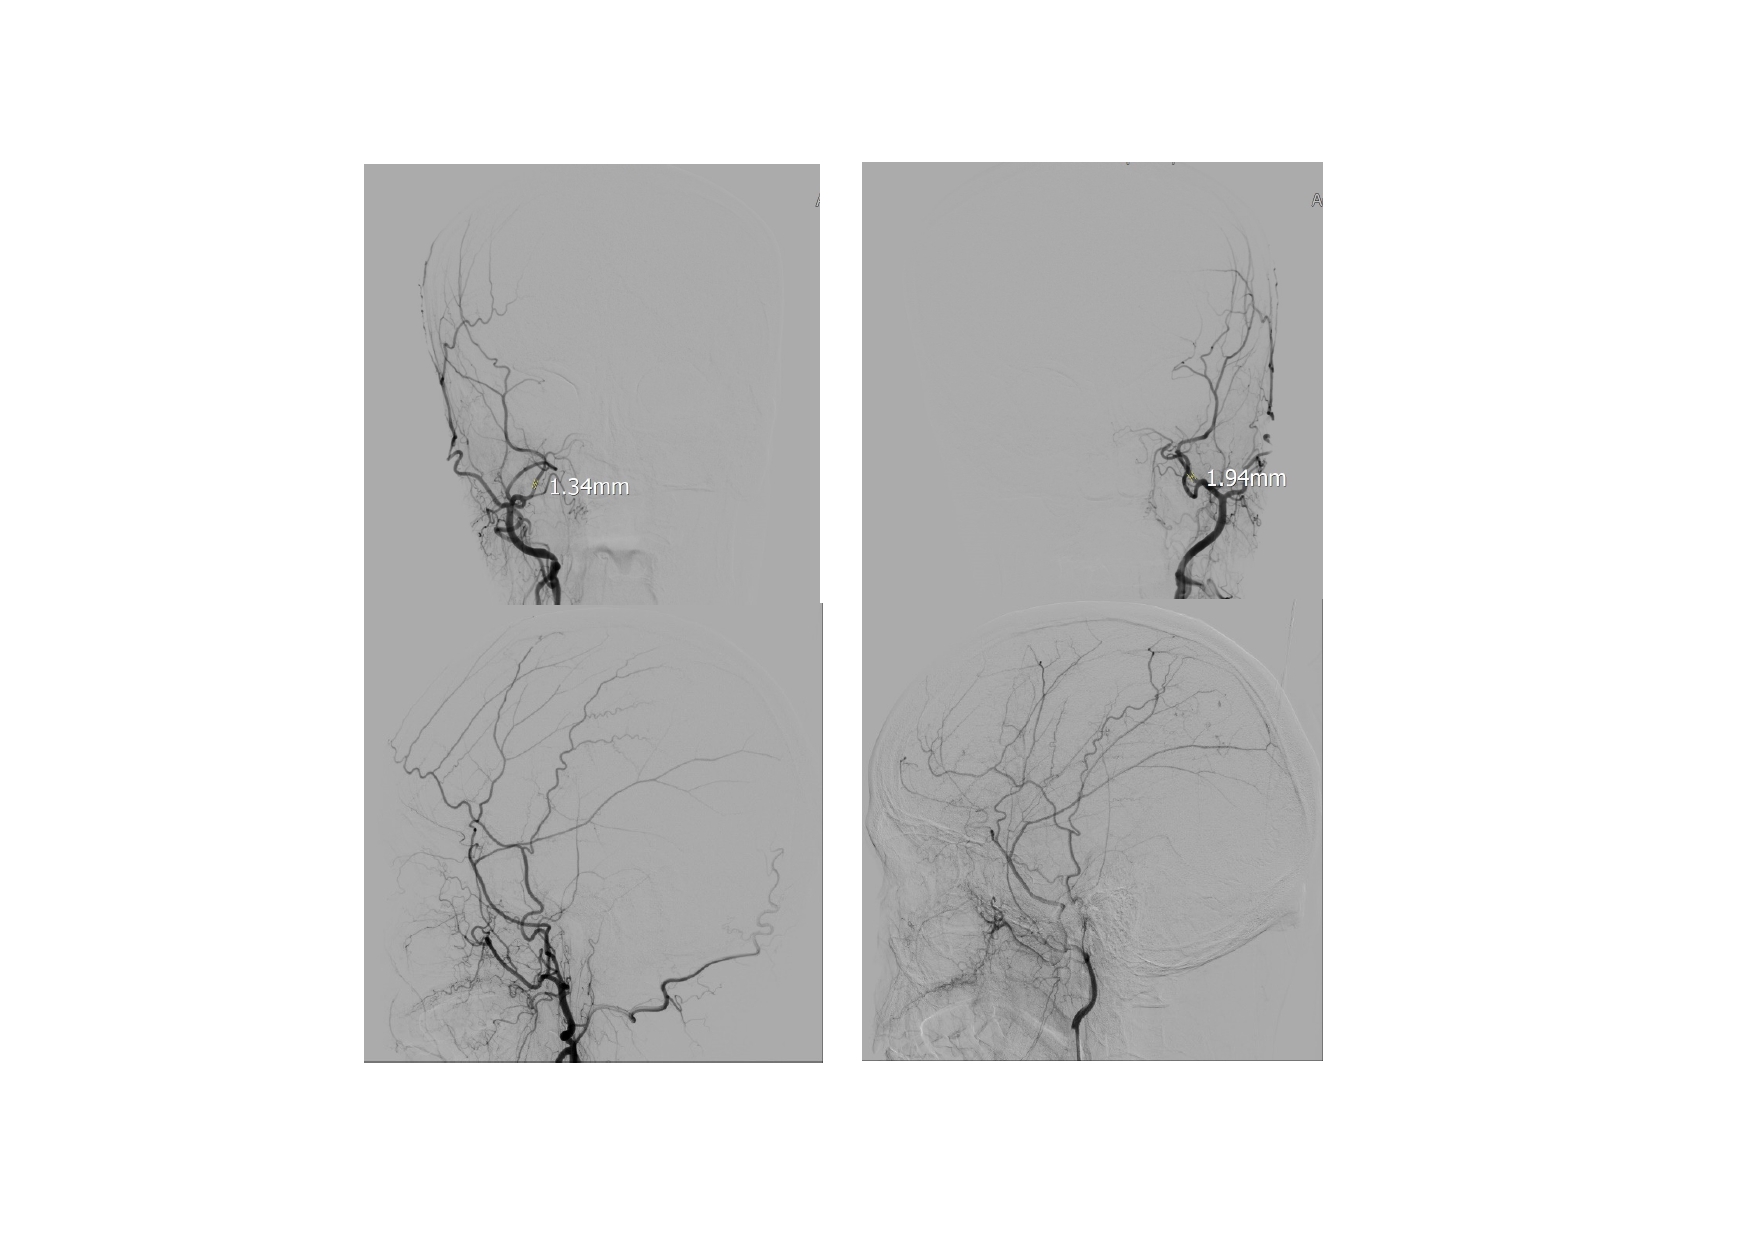

| 13:30 - 14:10 | Surgical management of skull base trauma Endovascular Management of Post-Traumatic Intracranial Vascular Lesions | Assoc. Prof. Nguyen Trong Yen Dr. Nguyen Ngoc Cuong | |

| 15:10 - 16:10 | Interactive Case Demonstration and Discussion II: ~20 minutes each, (5 minutes presentation followed by 15 minutes discussion) Practicals: How I am doing it? Participants present case presentations about how they do it? The faculty comment on and discussion. 1. Endoscopic approach in post-traumatic CSF leakage - Dr. Nguyen Thanh Xuan 2. Endovascular approach in CCF - Assoc. Prof. Le Thanh Dung | Prof. Christian Matula International & local faculties Participants | |